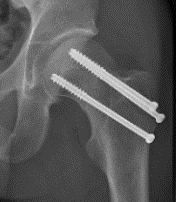

Fixation

DHS /Cannulated screws / FNS

Unstable fracture - augment with a medial buttress plate on inferior neck